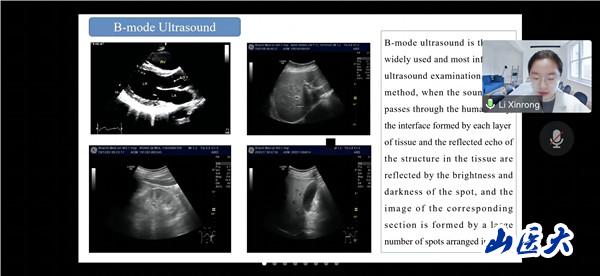

会议期间,俄罗斯沃罗涅日国立医科大学的三名学生代表分享了超声医学的演进历史,现代超声成像技术及容积超声诊断技术相关知识。我校第一医院高峰、第二医院王倩和医学影像学院李欣榕采用丰富的病例和图像展示了超声影像技术在肾功能疾病、脑颈动脉疾病和甲状腺疾病诊断和治疗中的应用。与会师生认真聆听、积极思考、踊跃提问,营造了学术思想碰撞、技术方法借鉴、疑难问题共析的浓厚氛围。